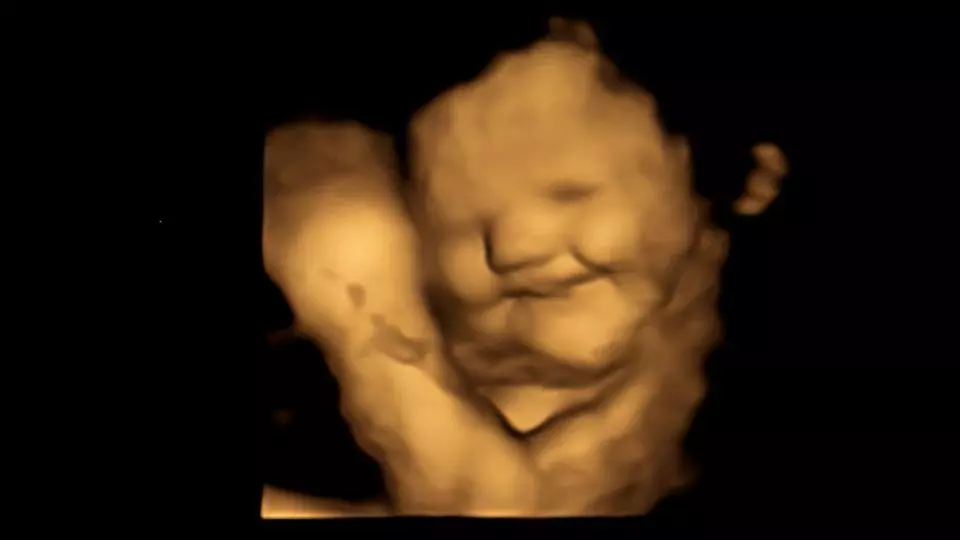

فقد أثبت العلماء أن الأجنة تتفاعل بشكل إيجابي قريب إلى الضحك داخل الرحم عند تذوقهم طعم الجزر الذي تستهلكه أمهاتهم، بينما يخلقون وجهًا يميل إلى العبوس عند تعرضهم للكرنب الأجعد Kale، وفقًا لدراسة نُشرت يوم الأربعاء الماضي في مجلة “سايكولوجيكال ساينس”.

وبعد فترة انتظار مدتها 20 دقيقة بعد الاستهلاك، خضعت الحوامل لفحوصات بالموجات فوق الصوتية رباعية الأبعاد، والتي تمت مقارنتها بالصور ثنائية الأبعاد للأجنة.